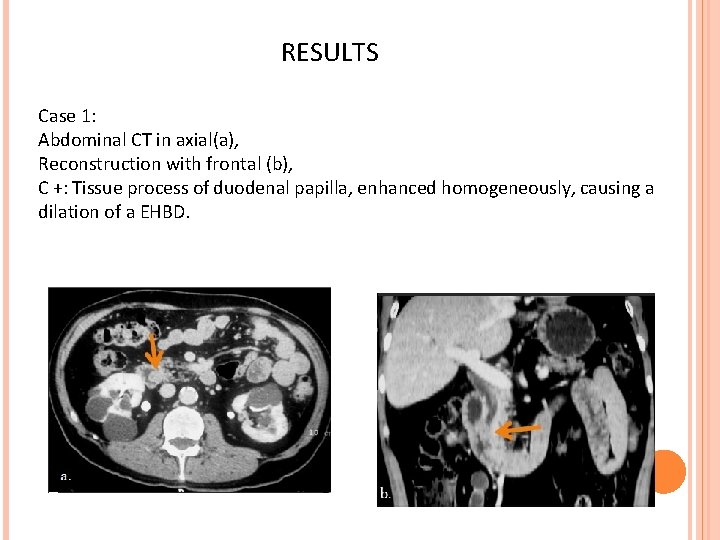

RESULTS Case 1: Abdominal CT in axial(a), Reconstruction with frontal (b), C +: Tissue process of duodenal papilla, enhanced homogeneously, causing a dilation of a EHBD.